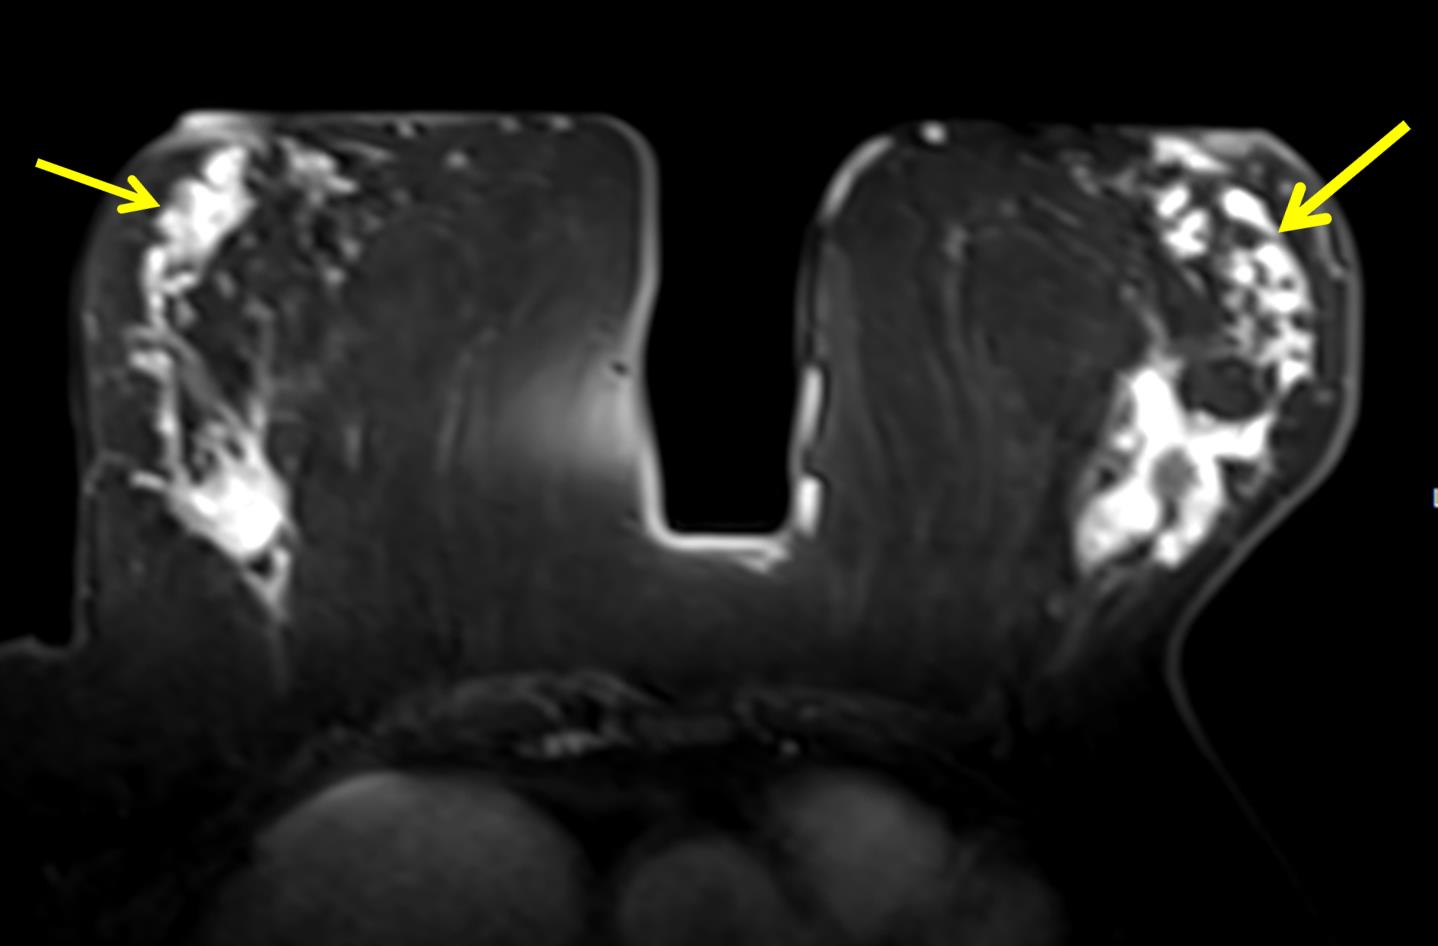

The most common cause of skin metastases in adult women is primary breast carcinoma, which comprises about 70% of cases [1]. Skin metastases have non-specific clinical appearances, making it challenging to differentiate them from other benign conditions [1]. We present a case of a 52-year-old female with type II diabetes and a three-month history of refractory skin lesions who did not respond to anti-inflammatory treatment. The patient subsequently complained of a right breast lump, evaluation of which led to the diagnosis of bilateral synchronous invasive lobular carcinoma.